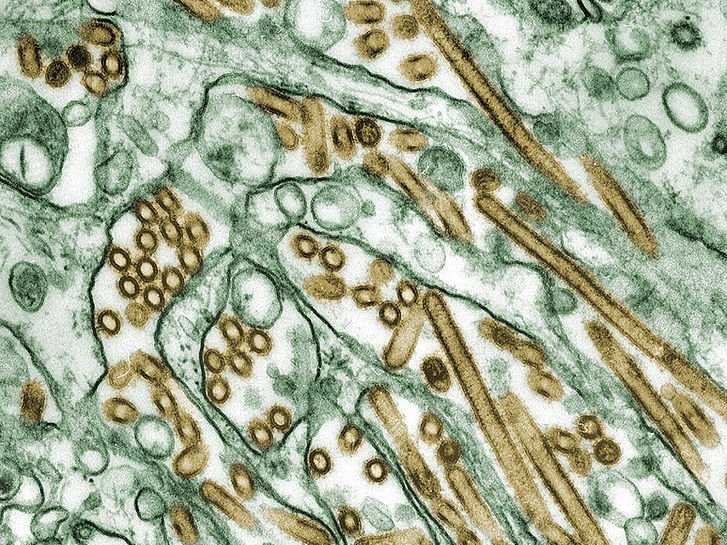

Gli scienziati cinesi hanno dato l’allarme mercoledì, dopo che un nuovo virus dell’influenza aviaria, H10N8, ha ucciso una donna anziana a dicembre e infettato un altro individuo il mese scorso.

“Il quinto ceppo influenzale emerge in 17 anni. Il virus ha un profilo genetico preoccupante e deve essere strettamente controllato”, hanno riferito gli scienziati cinesi sulla rivista medica Lancet.

Il virus sembra di essere in grado di infettare il tessuto profondo nei polmoni e può avere caratteristiche che permettono la sua diffusione in modo efficiente tra gli esseri umani.

Profilo genetico del virus

Nel genoma di H10N8, sono rimescolate geni da virus H9N2, secondo gli autori.

Il genoma di H10N8, reca una mutazione nella proteina PB2 che suggerisce una capacità di adattarsi ai mammiferi.

Il virus ha anche una mutazione nella proteina emoagglutinina – un picco sulla superficie del virus che consente di bloccarsi su altre cellule – e che suggerisce che può infettare in profondità i polmoni, come H5N1, piuttosto che il tratto respiratorio superiore, la trachea .